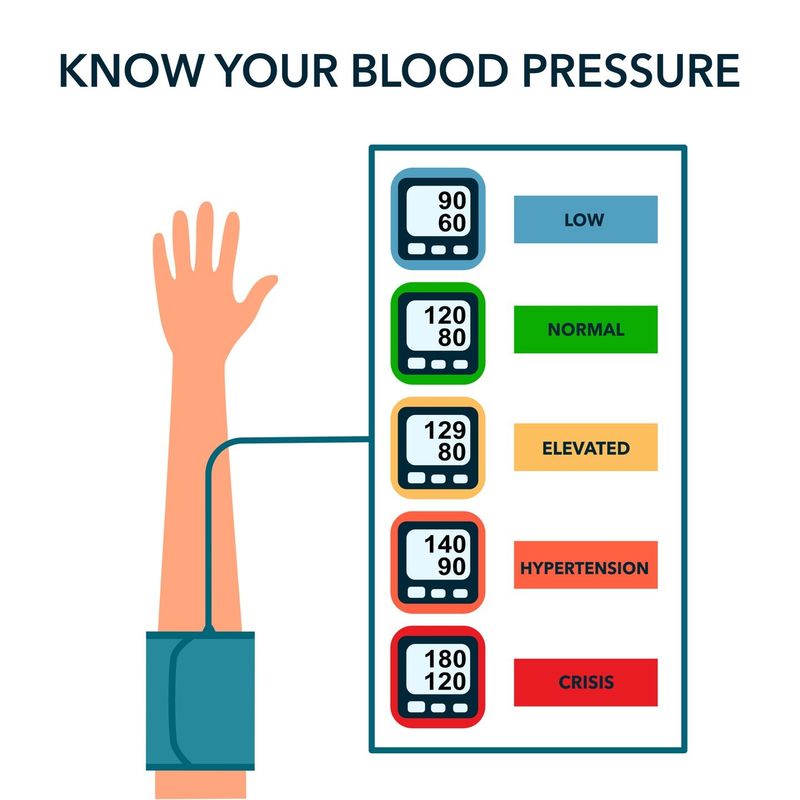

15. High Blood Pressure

Blood pressure readings creeping upward could signal too many carbs. Diets high in sugar can affect blood vessel elasticity, raising blood pressure.

Adopting a heart-healthy diet with fewer refined sugars and more whole foods can support better blood pressure levels. This conscious dietary adjustment contributes to cardiovascular health, ensuring your heart beats strong and steady.